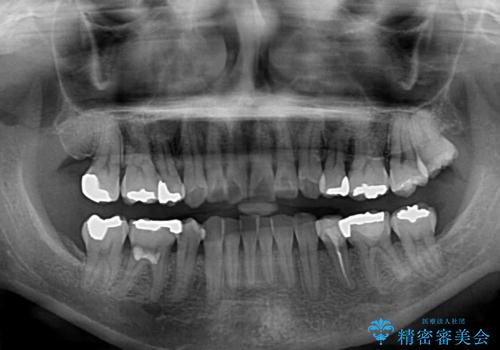

- 上下前歯の叢生を気にして来院された患者様です。

費用を抑え、期間もあまりかけずに治療をしたいとのことで、インビザライン・ライトを用いて矯正治療を行うこととしました。

矯正治療後には、下顎臼歯の目立つ銀歯をセラミックインレーにて修復治療を行いました。